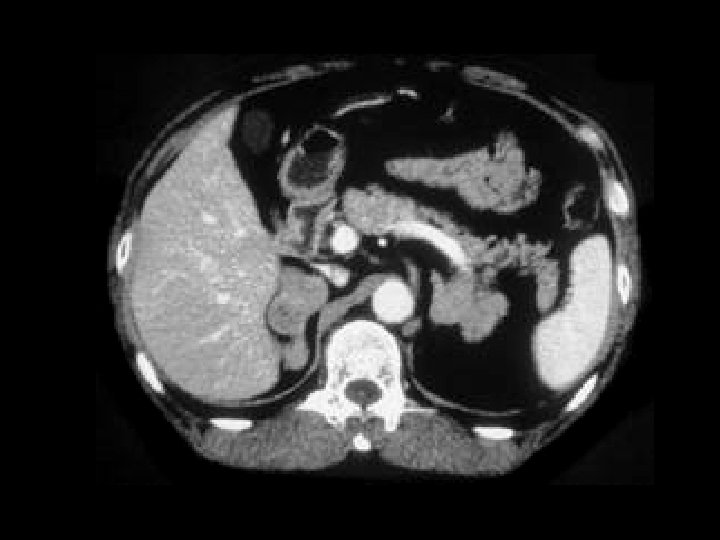

Lymphoma • Findings: – Innumerable low density lesions of the liver and one in the spleen • ddx: – Metastatic disease – Fungal abscesses